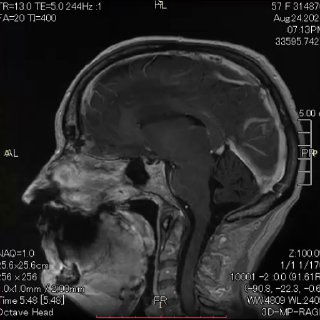

Рецидив метастаза рака молочной железы в зоне предыдущего удаления.

Выраженный перифокальный отёк мозга привёл к грубому гемипарезу.

После удаления очага неврологический дефицит практически полностью регрессировал.

Иногда даже при агрессивном течении заболевания вмешательство даёт пациенту не просто время, а качество жизни. На видео - МРТ до и после удаления.